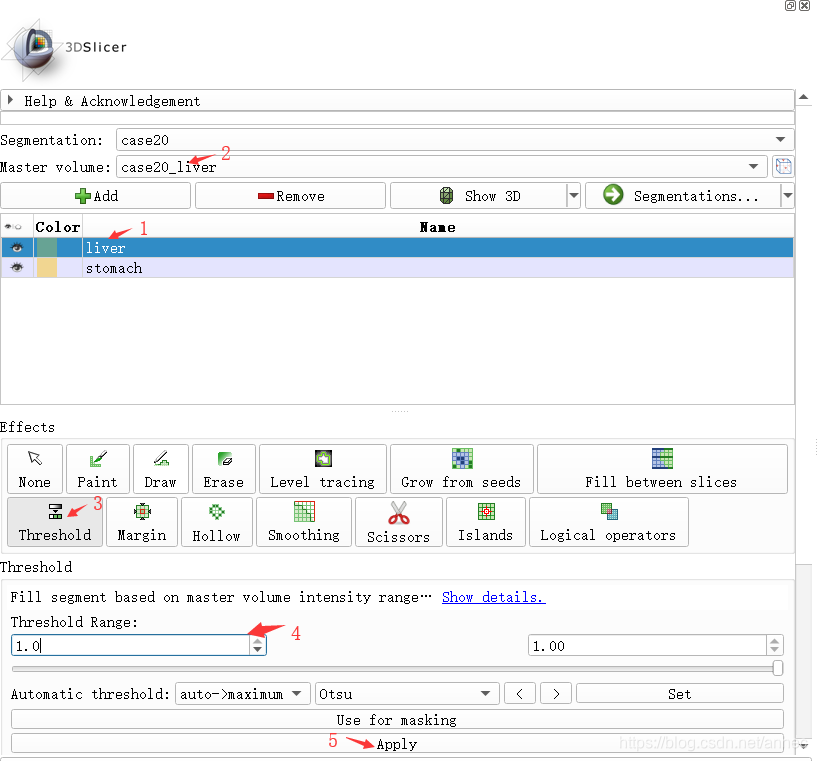

将原始体数据和多个label的.nii同时打开,然后在Segment模块中,首先新建一个Segmentation,然后为每一个label添加一个Segment,具体方法为:

- 选中一个Segment;

- 选择labeld对应的Volume;

- 点击Threshold工具;

- 设置高低阈值为label的值(可将鼠标在右侧可视化图中移动,左下角会显示当前鼠标位置的灰度值);

- 点击apply。